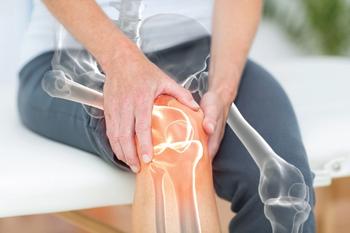

Additional advancements in how radical prostatectomy is performed are needed to improve other urinary outcomes such as good urinary function and social incontinence.